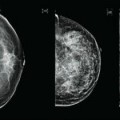

Μύθοι για τον μαστό

O Οκτώβριος είναι μήνας ενημέρωσης για τον καρκίνο του μαστού. Αν και βαίνει στο τέλος του, ο τακτικός έλεγχος και η ενημέρωση δε θα πρέπει να περιορίζεται σε ένα μήνα του χρόνου. Το σύνθημα για φέτος είναι η ενημέρωση για την πυκνότητα του μαστικού ιστού. Το 45% των γυναικών στην Αμερική δεν ξέρουν αν […]